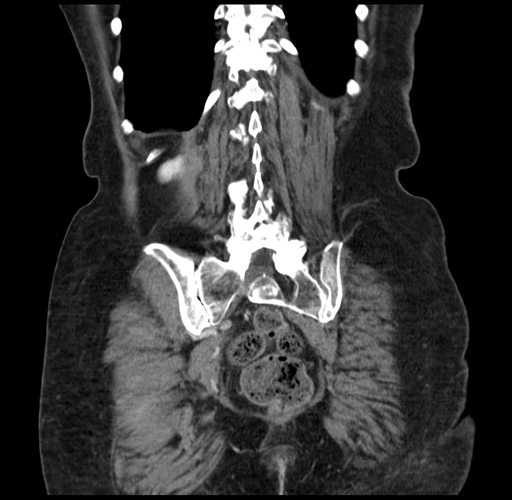

Pre-Chemo: Coronal Venous

Coronal Venous